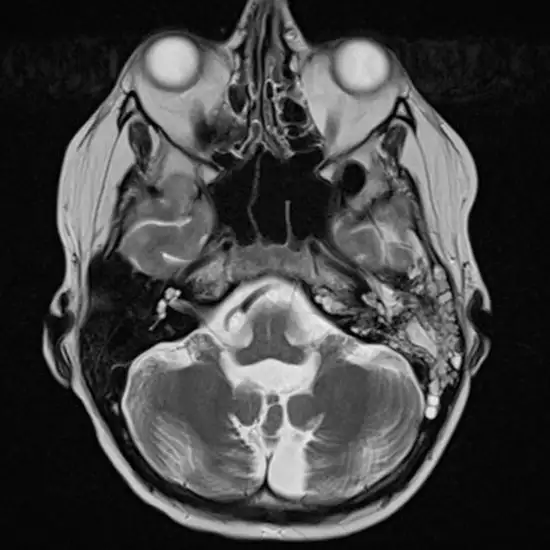

A doctor can perform a thorough examination of your ear and mastoid area. They may use tools like an otoscope to get a better look inside your ear. In some cases, they might order imaging tests like an X-ray or CT scan to get a clearer picture of what’s going on.